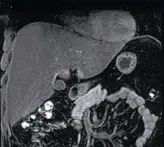

МРТ внутренних органов с возможностью онкологических исследований.

Уникальная технология – МРТ сосудов, отходящие от аорты. Сосуды почек.

Органы малого таза – предстательная железа, матка…